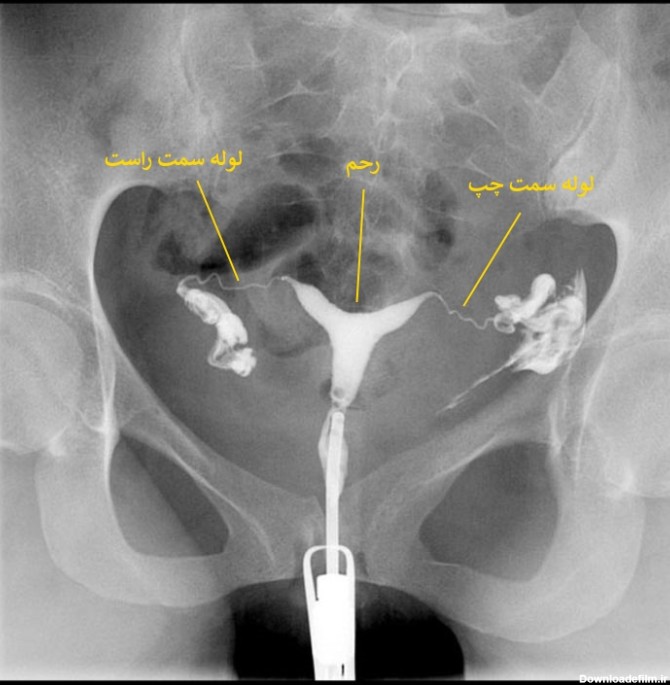

عکس رنگی رحم یا هیستروسالپنگوگرافی روشی جهت تصویربرداری با اشعه ایکس از رحم و لوله های آن است که با تزریق ماده حاجب به آن، در تصاویر رادیولوژی رحم را رویت پذیر کرده و بررسی ناهنجاریهای آن را توسط رادیولوژیست ممکن میسازد.

عکس رنگی رحم بدون درد؛ هیستروسالپنگوگرافی برای مشاهده داخل رحم و لوله های فالوپ استفاده می شود. می تواند نشان دهد که داخل رحم اندازه و شکل طبیعی دارد یا خیر.

چگونگی گرفتن عکس رنگی از رحم به این ترتیب است که به پشت دراز میکشید و زانوها را خم و پاها را باز میکنید مثل زمانیکه برای معاینه به پزشک زنان مراجعه میکنید